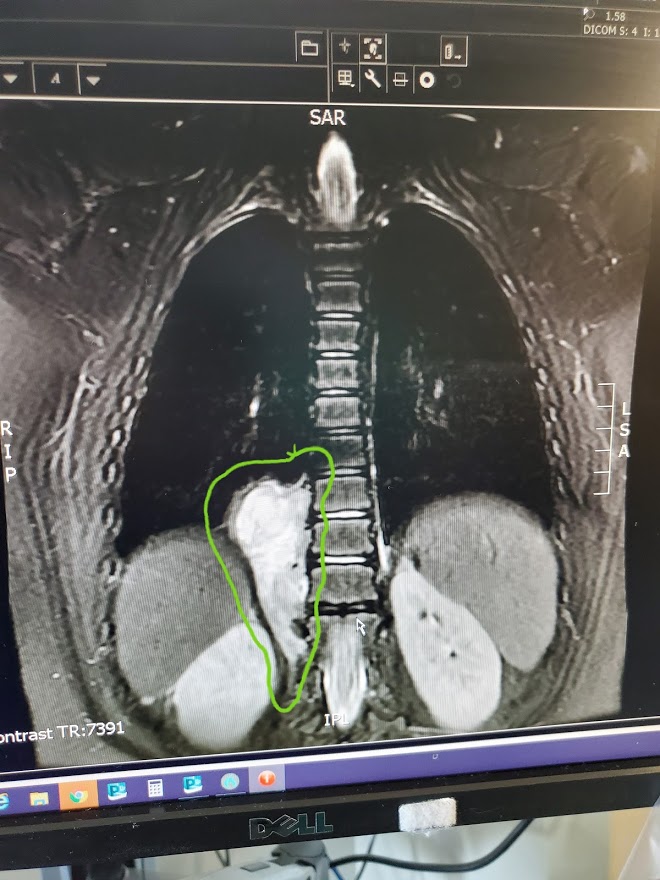

Then, on October 26, we returned to the Children’s Hospital with our little girl to have a tumor measuring 8cm x 4cm x3.5 removed from along her little spine.

Savannah’s tumor, ‘Mr. Bad Boy’, is a Ganglioneuroblastoma with intermixed sub types. What is that? A Ganglioneuroblastoma is a tumor that has both malignant and benign cells that started to grow along a ganglion nerve along her spine. ‘Mr. Bad Boy’ has been there for a long time. Likely, this tumor started growing when our little lady was just 1 or 2 years old. ‘Mr. Bad Boy’ was slow growing at first so he didn’t allow us to see any evidence that he was there. He grew into a monster that was somewhere on the spectrum of a Malignant Neuroblastoma, a cancerous growth the requires chemo or radiation typically found and diagnosed between the ages of 2 or 4. We did not find him when he was mean and full of rage. Instead, he stayed well hidden.

So what now? We wait and we watch. Yes, some of the tumor was left in her body because the risk was to high to remove it without damaging something else. Yes, there may still by malignant cells in there, but it is likely that they already have changed or know that they need to differentiate. She will follow up with more scans consistently over the next 2 years to watch for growth. In the mean time, we help her heal. We watch the miracles still unfold as her little body gets ready to feel better than it has in years. Her future is bright and beautiful. Her spirit is strong. Her faith is strong.